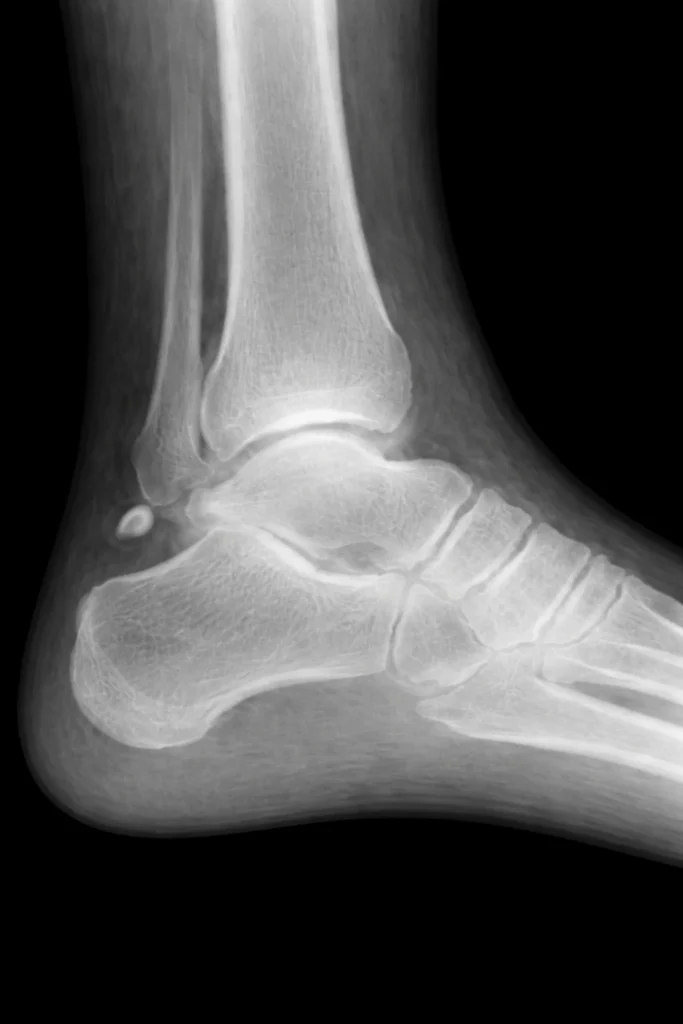

Fontos tudni, hogy nem törések, és nem is „rosszul összeforrt” csontok. A töréssel szemben a járulékos csont sima szélű, rendezett szerkezetű, míg a törés általában éles, szabálytalan kontúrt mutat.

A diagnózis alapja legtöbbször röntgenvizsgálat, amely jól elkülöníti a járulékos csontokat más eltérésektől. Szükség esetén MR-vizsgálat segíthet megítélni a környező inak és lágyrészek állapotát.

A járulékos csont összetéveszthető töréssel?

Igen, ezért fontos a szakorvosi értékelés. A járulékos csont röntgenen többnyire simább, kerekebb, rendezett szélű, míg egy törés gyakran szabálytalan, éles szélű. Gyermekeknél esés vagy sportbaleset után különösen lényeges a pontos elkülönítés.